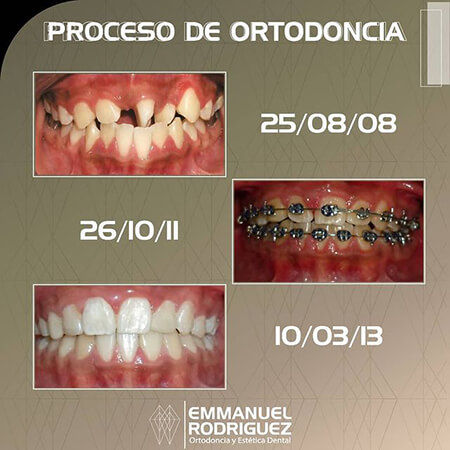

Before and After Gallery